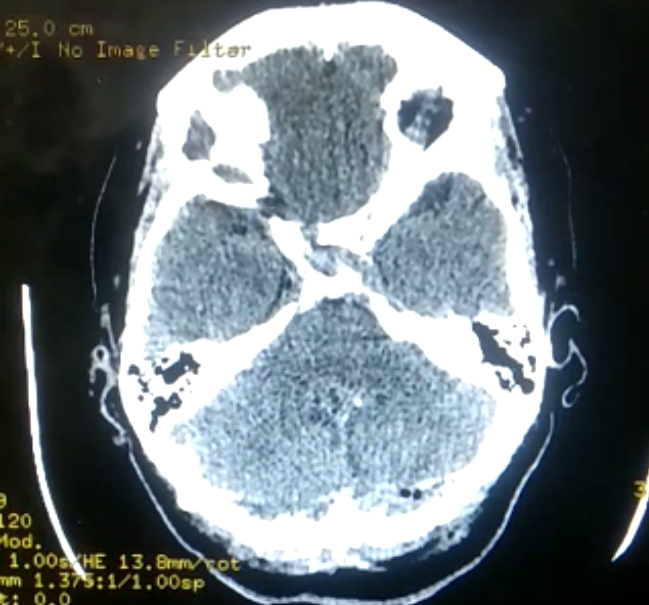

Figure 3 Cross-section of the brain showing the March 30 edema.